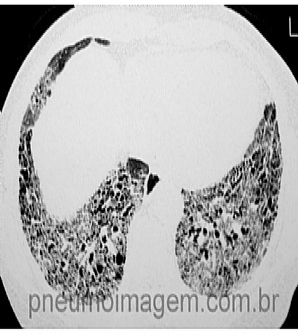

Veja imagens sobre Fibrose Pulmonar Idiopática no PneumoImagem, clique aqui.